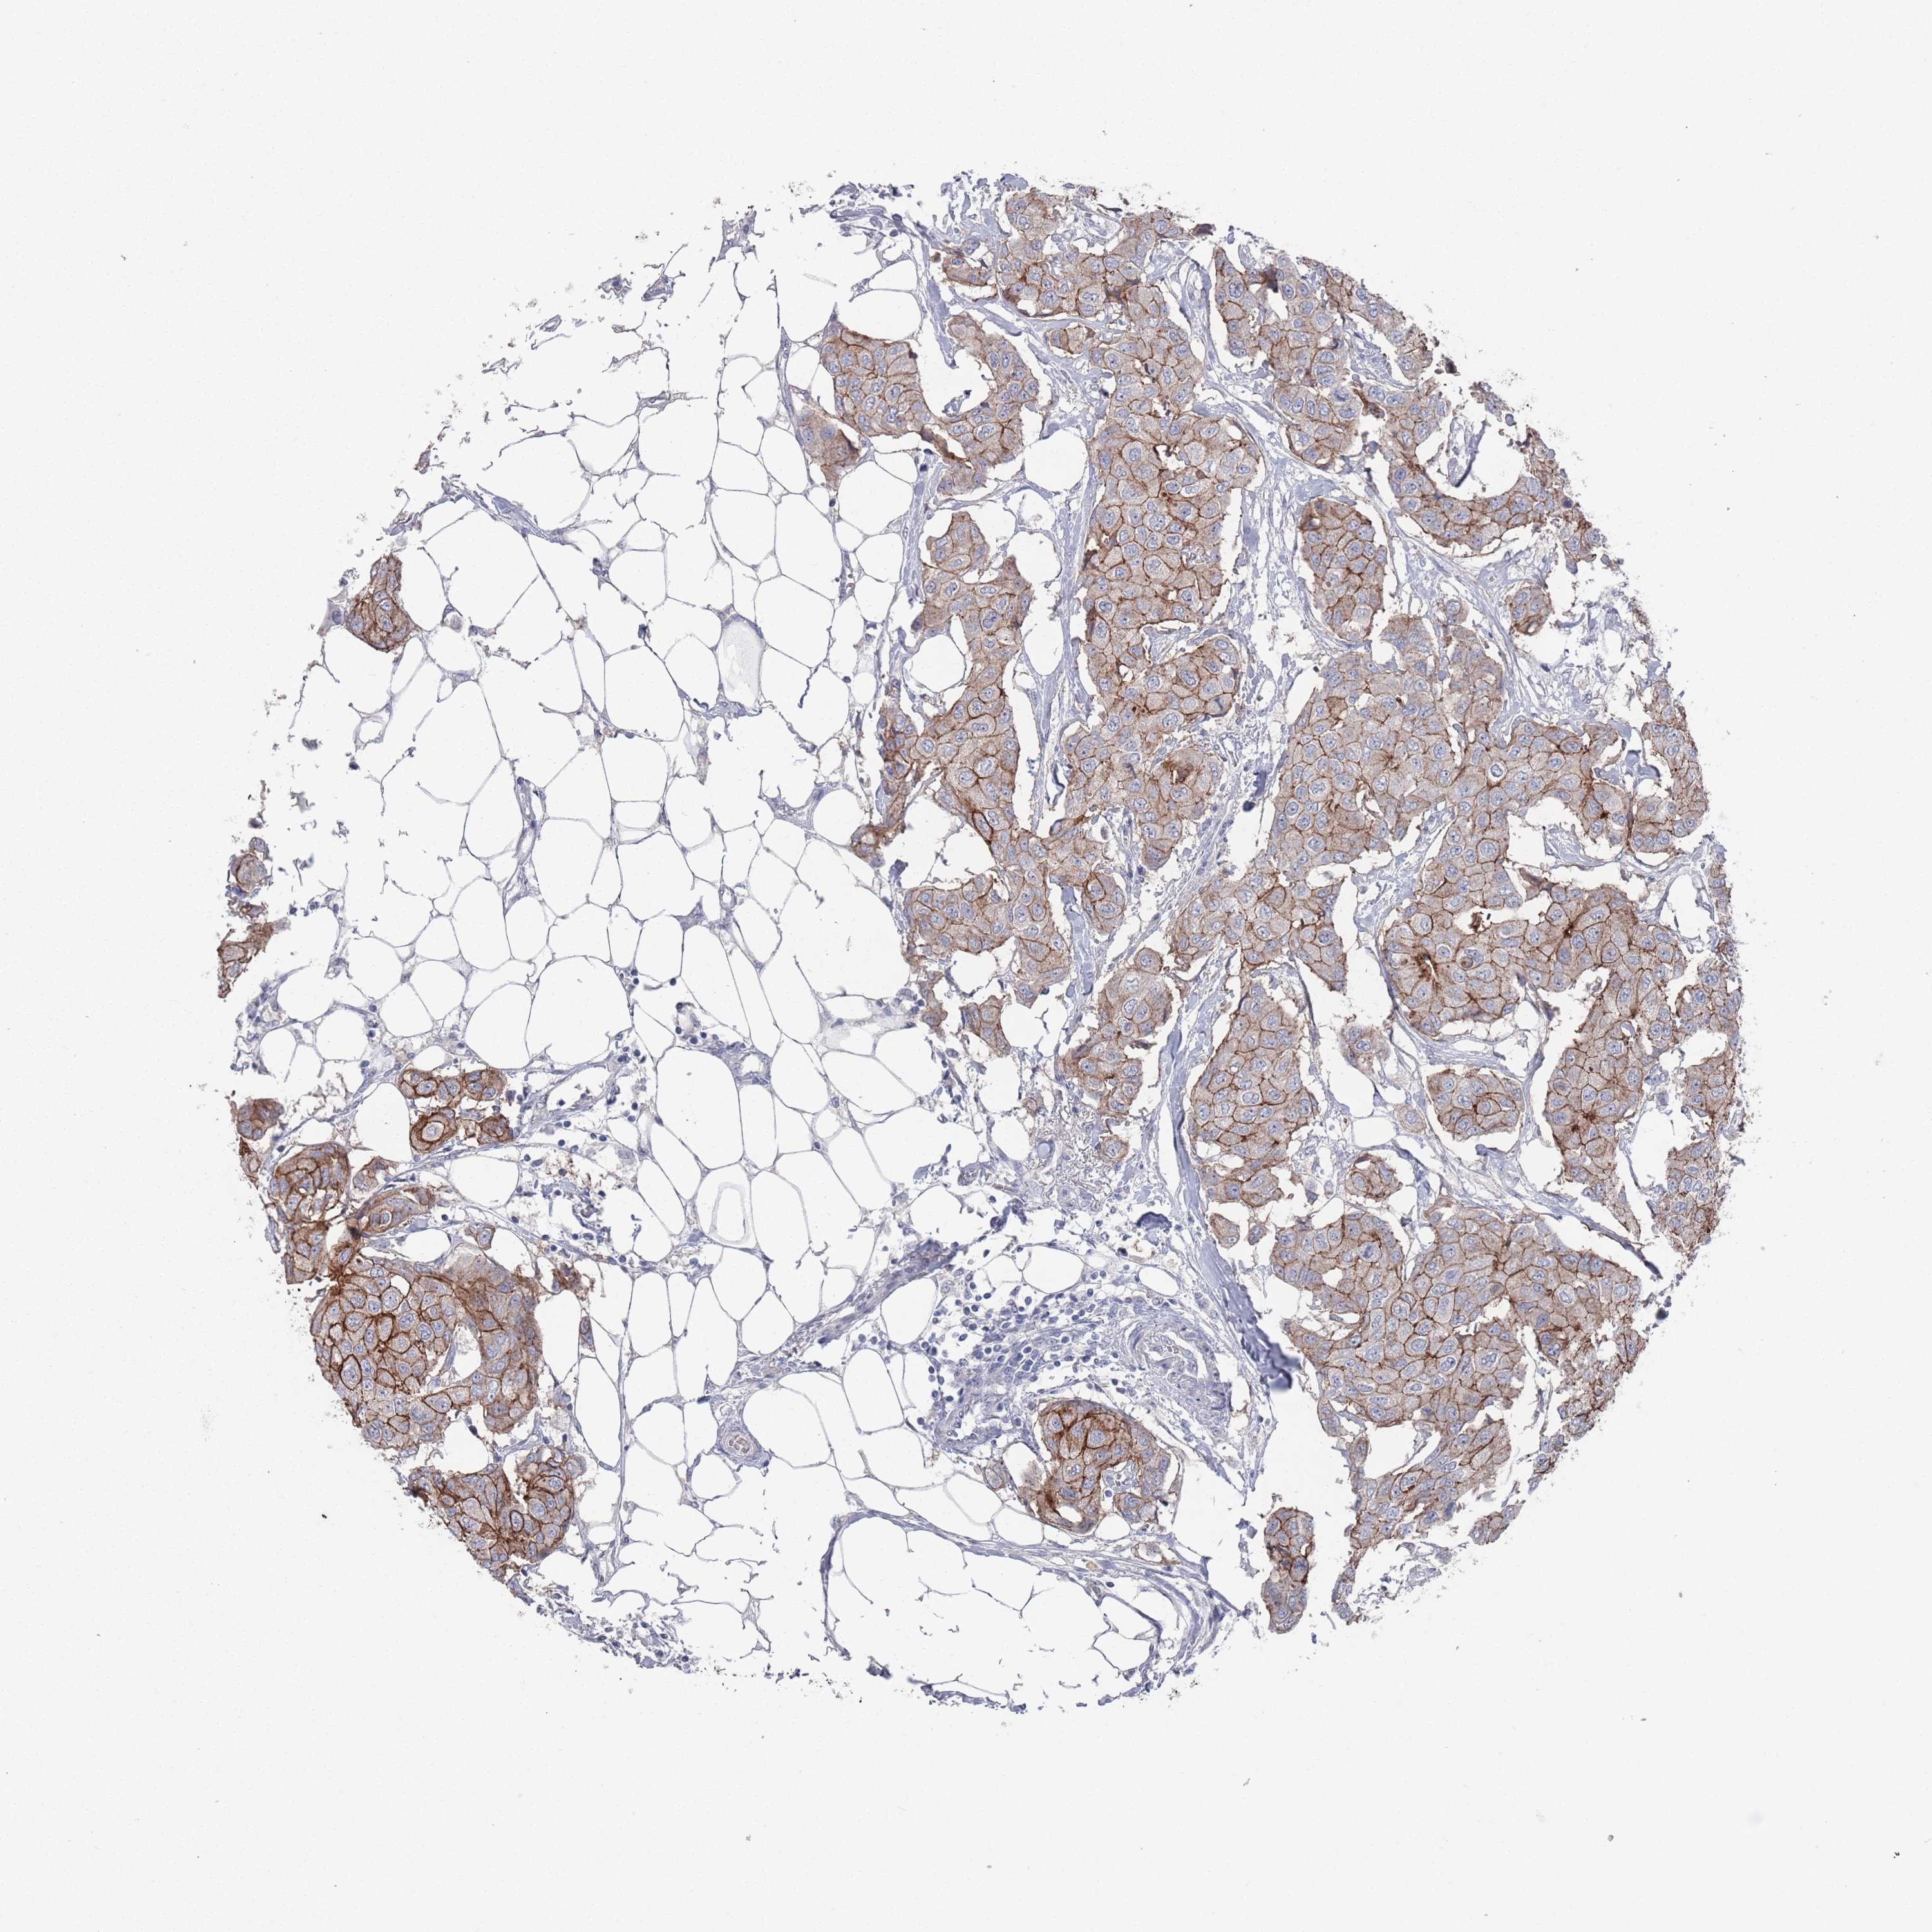

CANCER BREAST CANCER Show tissue menu

BRCA TCGA BRCA VALIDATION PROTEIN EXPRESSION